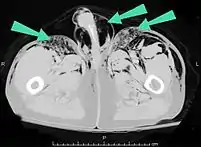

من السهل تشخيص الحالات الكبيرة من نفاخ تحت الجلد بسبب العلامات المميزة لهذه الحالة.[1] في بعض الحالات، تكون العلامات خفية مما يجعل التشخيص أكثر صعوبة.[11] يُستَخدم التصوير الطبي لتشخيص الحالة أو لتأكيد التشخيص السريري. في الصورة الإشعاعية الصدرية، قد يظهر نفاخ تحت الجلد كحزوزٍ إشعاعيةٍ شفافة في النمط المتوقع لمجموعة العضلات الصدرية الكبرى. قد يتداخل الهواء في الأنسجة تحت الجلدية مع التصوير الإشعاعي للصدر، مما يُخفي حالاتٍ خطيرة مثل استرواح الصدر.[26] قد يقلل أيضًا من فعالية الموجات فوق الصوتية في الصدر.[27] من ناحية أخرى، بما أن نفاخ تحت الجلد قد يظهر بوضوح في الأشعة السينية للصدر قبل أن يحدث استرواح الصدر، يمكن استخدام وجوده للدلالة على حدوث الإصابة الأخيرة.[11] يمكن رؤية النفاخ تحت الجلد أيضًا في الأشعة المقطعية، حيث تظهر تجمعات الهواء تحت الجلد كمساحاتٍ مظلمة. يُعتبر التصوير المقطعي دقيق جدًا، حيث يجعل من السهل العثور على البقعة الدقيقة التي يدخل منها الهواء إلى الأنسجة الرخوة.[11] في عام 1994، نشر ماكلين مزيدًا من الأفكار حول الفيزيولوجيا المرضية لمتلازمة ماكلين التلقائية، والتي تحدث نتيجة لنوبةٍ حادةٍ من الربو.